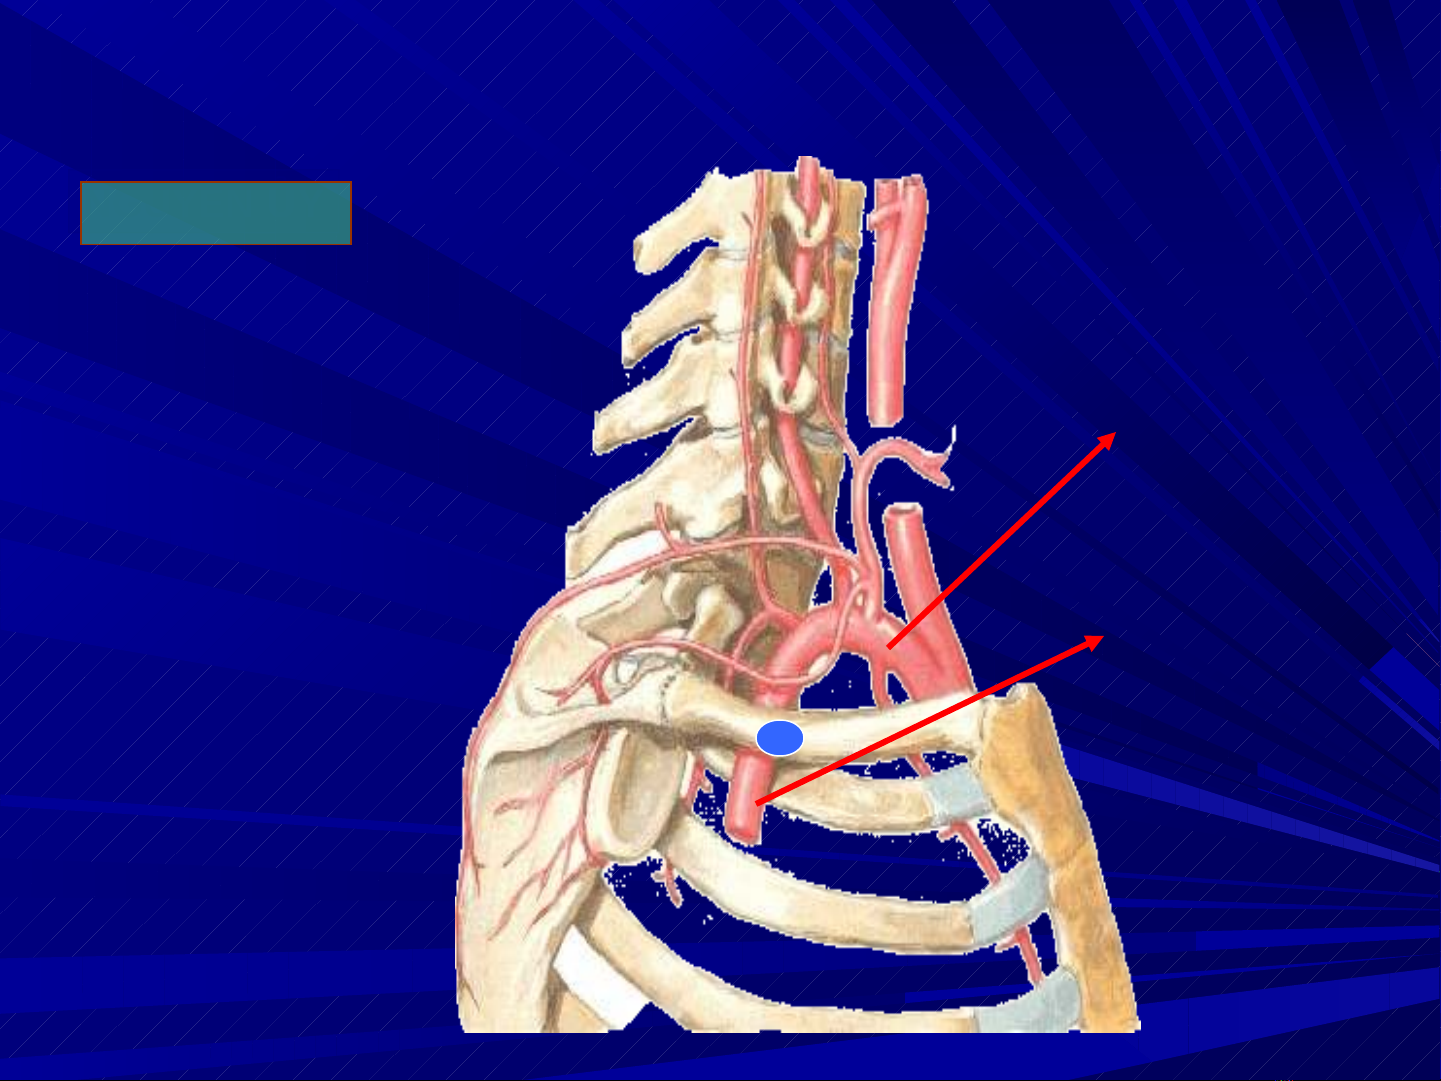

Đ NG M CHỘ Ạ

D I ĐÒN(P)ƯỚ

Đ NG M CHỘ Ạ

CHI TRÊN

NGUYÊN YỦ

NGUYÊN YỦ